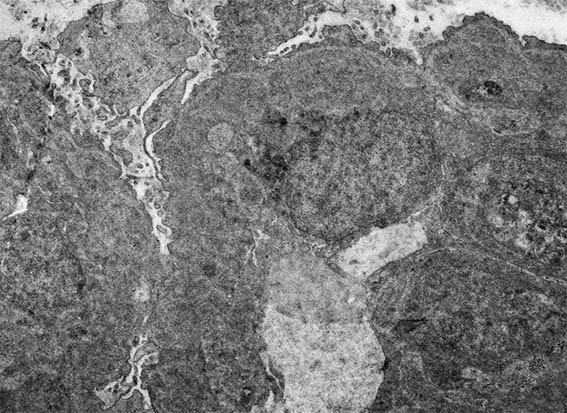

H&E, X400.

Figura 11. Microscopía electrónica, aumento original, X4.000. Observe el daño podocitario extenso, el severo engrosamiento de las paredes capilares, aumento de las células endoteliales y áreas más electron-densas subendoteliales.